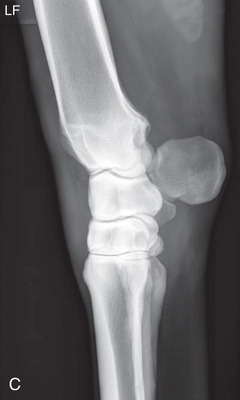

| Stifle | Lateromedial (LM) | Lateral (L) |

| Caudoproximal-craniodistal (CdPr-CrDi) | Caudocranial (CdCr) | |

| Lateral trochlear ridge and medial femoral condyle (stifle) | Caudoproximal 60-degree lateral–craniodistomedial oblique (Cd60L-CrMO) | CdLCrMO |

| Optional stifle | Cranioproximal-caudodistal (CrPr-CdDi) | Craniocaudal (CrCd) |

| Cranioproximal-craniodistal oblique(CrPr-CrDiO) | Skyline patella | |

| Lateromedial flexed (LM) | Flexed lateral (L) |

Radiography of the femorotibial joint (stifle) is difficult because of the thickness of the surrounding tissue and the sensitive nature of this region. Because of the depth of the muscle in the femoral region, the caudocranial projection demonstrates little above the joint space. Radiographs of this region should be attempted only if the patient is cooperative. Safety is paramount in radiography of the hind region of the horse. Sedation or a twitch may be used; general anesthesia is also to be considered.